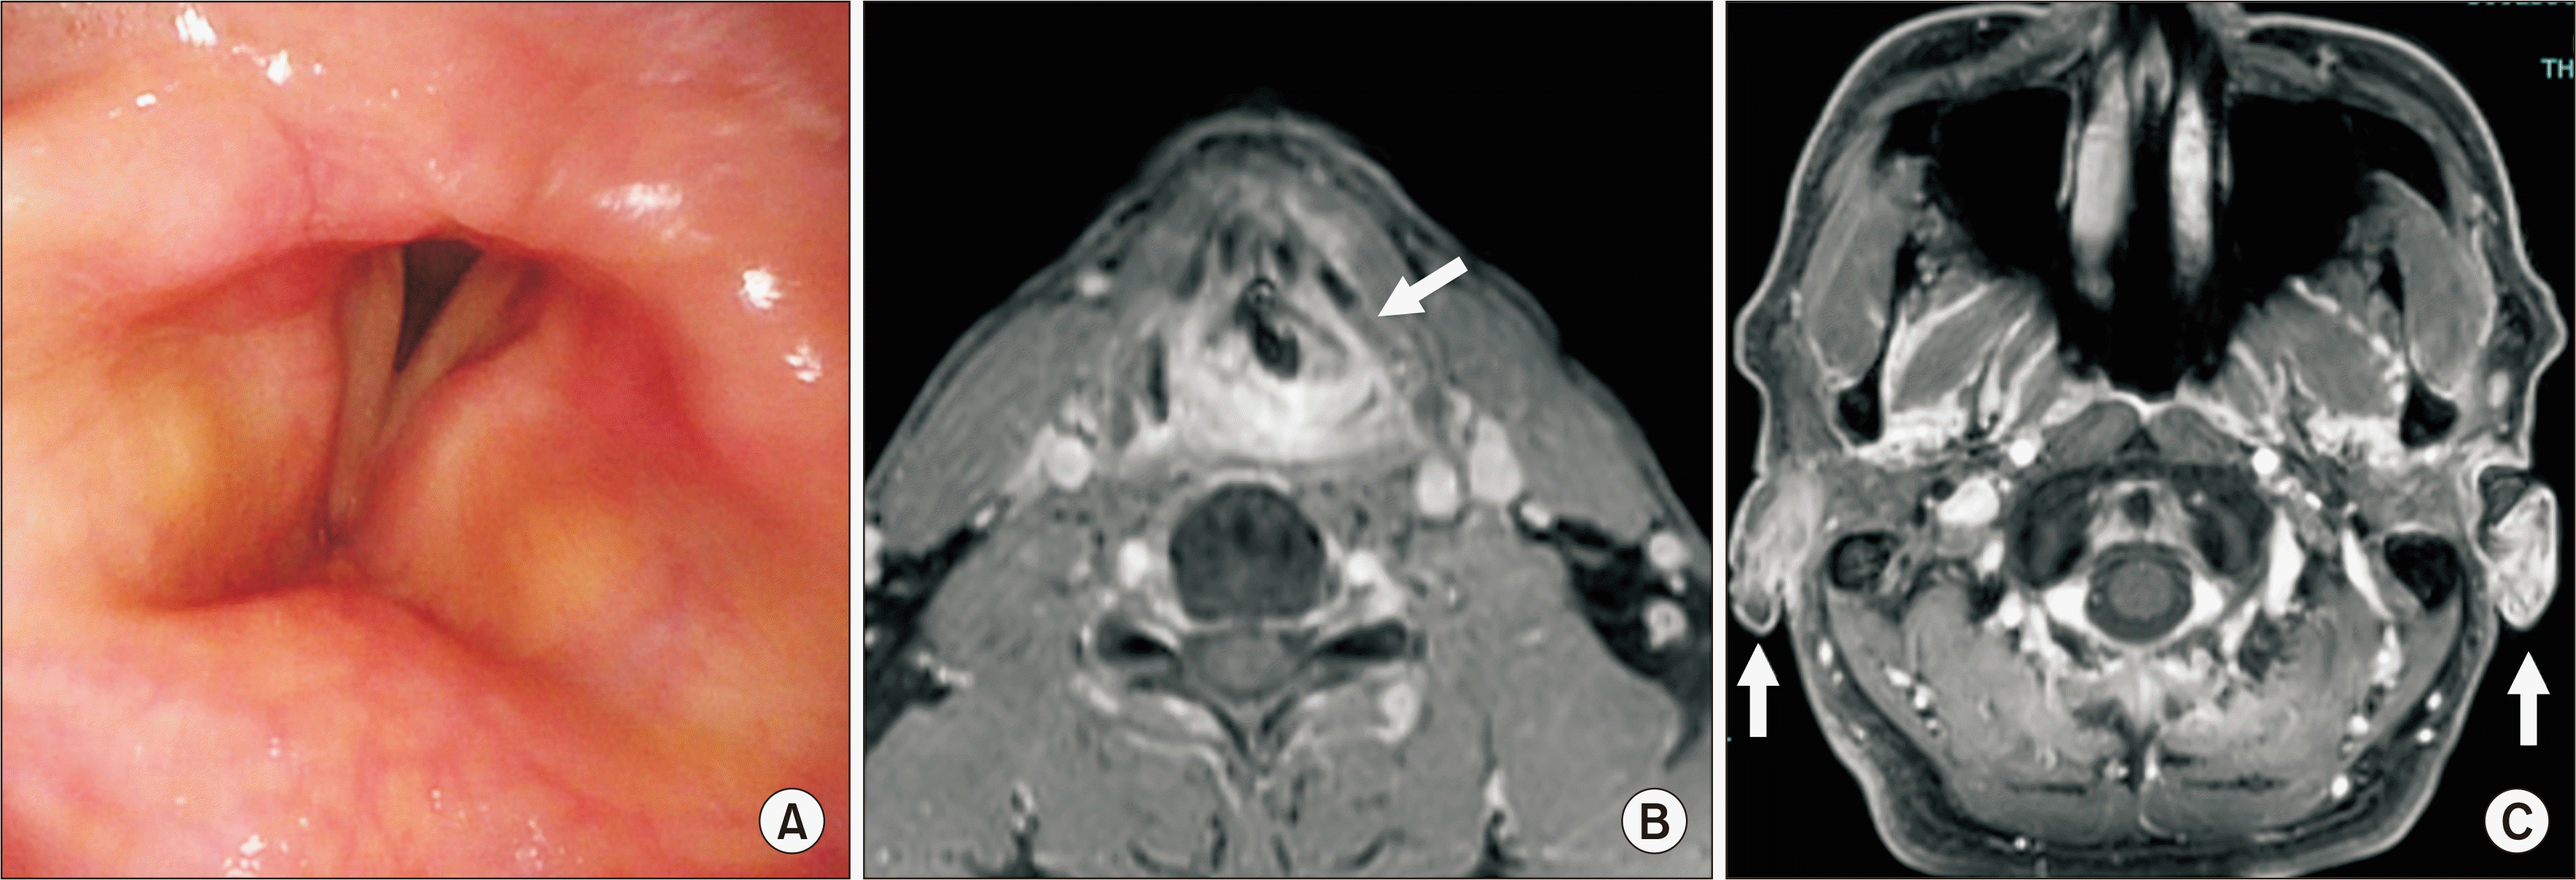

Upon presentation to our department, the patient described hoarseness and difficulty breathing with exertion. Physical examination revealed oral ulcers and a skin rash similar to folliculitis on his left lower leg, but genital ulcers and auricular abnormalities were not observed. Laboratory investigation revealed a normal erythrocyte sedimentation rate and C-reactive protein level; autoantibodies (including rheumatoid factor, antinuclear antibody, and antineutrophil cytoplasmic antibody) were not detected. Viral tests for hepatitis B virus, hepatitis C virus, and human immunodeficiency virus, along with a T-SPOT test for mycobacterial infection, were all negative. Furthermore, electromyography tests on the sternocleidomastoid and orbicularis oris muscles were normal, and a repetitive stimulation study of the facial and accessory nerves showed no evidence of waning. Serologic HLA analysis demonstrated A24, A26, B54, and B61. Laryngoscopy revealed bilateral vocal fold immobility with impairment of adduction and abduction (Figure 1A and Supplementary Video 1). Contrast-enhanced magnetic resonance imaging (MRI) demonstrated inflammation in the cricoid and arytenoid cartilages, the surrounding tissue, and bilateral auricular cartilages (Figure 1B and 1C). We could not biopsy the patient’s laryngeal cartilage because he did not give consent, and histologic examination of an auricular cartilage biopsy did not reveal chondritis. He met the diagnostic criteria for BD established by the Behçet’s Disease Research Committee of Japan [3] and had auricular and laryngotracheal chondritis detected by MRI.

Figure 1

Laryngoscopy and magnetic resonance imaging (MRI) before treatment. (A) Laryngoscopy reveals restricted abduction of both vocal cords on inhalation. (B, C) Contrast-enhanced MRI demonstrates thickening and increased enhancement of the arytenoid and cricoid cartilages (B, indicated by the arrow) and bilateral auricular cartilages (C, indicated by the arrows).